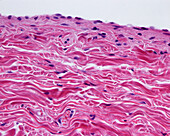

13613516 - Vein adventitia, light micrograph